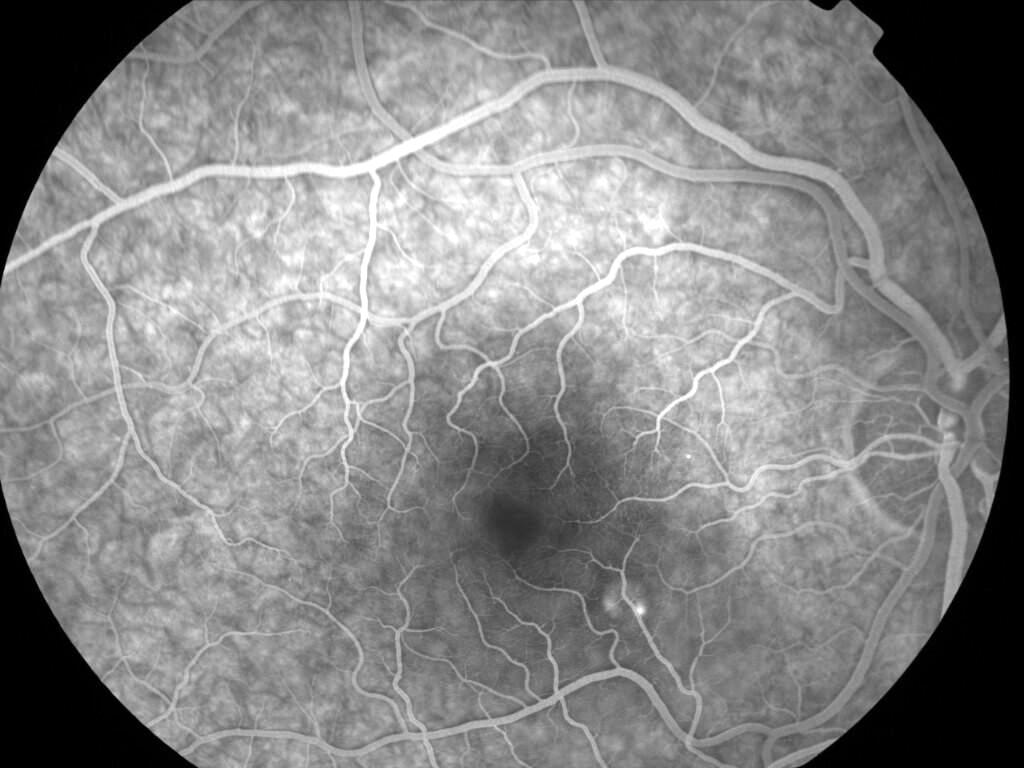

IM000005.jpg